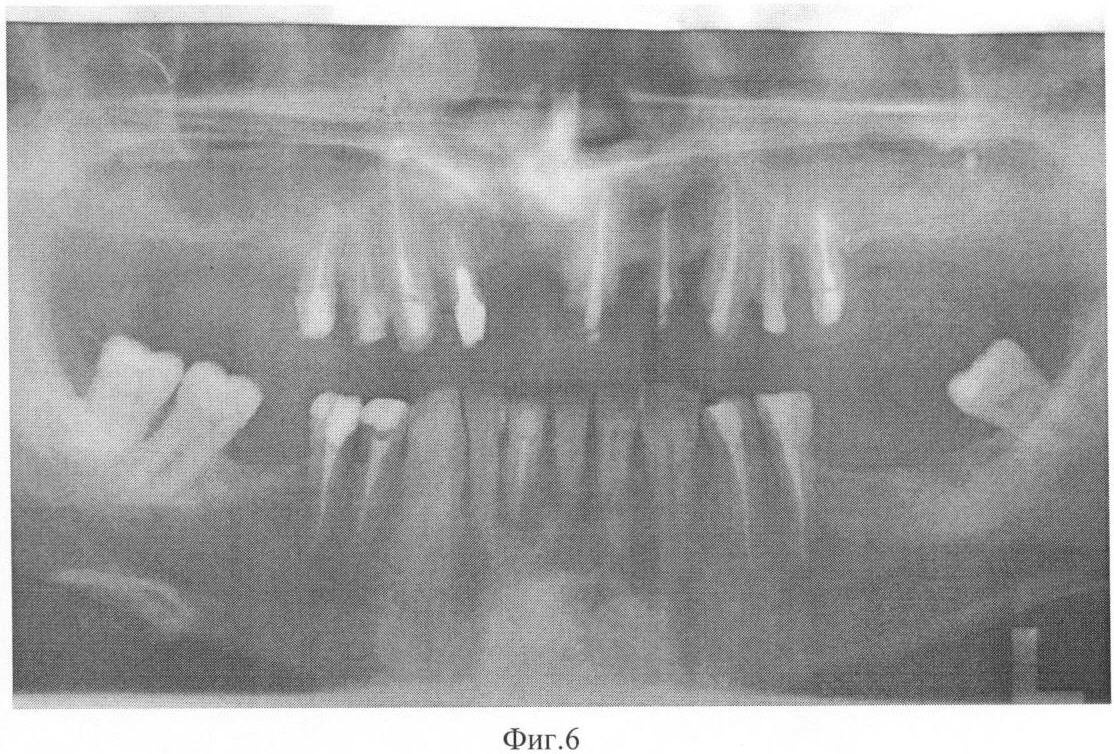

На фиг.5 представлена рентгенограмма пациента 3 до лечения.

На фиг.6 – рентгенограмма пациента 3 после лечения, проведенного без коррекции минерального обмена.

Пример 3. Больной М., 1964 года рождения, обратился на кафедру терапевтической стоматологии ФПДО Московского государственного медико-стоматологического университета с жалобами на подвижность зубов, затрудненное пережевывание пищи, боль в деснах при чистке зубов и приеме пищи. Ранее лечился у пародонтолога в поликлинике по месту жительства. Лечение заключалось в снятии зубных отложений, проведении противовоспалительной и антимикробной терапии, протезировании. Практически здоров. Профессиональных вредностей нет, аллергию и гепатит отрицает.

Осмотр полости рта. Слизистая оболочка десны отечна, гиперемирована с синюшным оттенком, при пальпации выделяется гнойный экссудат в области всех зубов. Подвижность зубов II-III степени. Жевательная группа зубов на верхней челюсти удалена по поводу пародонтита. При зондировании в области фронтальных зубов верхней и нижней челюсти определяются пародонтальные карманы глубиной 7-8 мм. Имеется мелкое преддверие полости рта со снижением уровня прикрепленной десны за счет множественных рецессий. Гигиена полости рта удовлетворительная. Наличие обильных поддесневых зубных отложений. Прикус ортогнатический.

Данные рентгенологического исследования. На ортопантомограмме верхней и нижней челюстей определяется убыль костной ткани межальвеолярных перегородок за счет резорбции на 1/2 и более длины корня в области зубов верхней челюсти и в пределах 1/2 длины корня в области нижних зубов.

Данные лабораторных исследований. Клинический анализ крови в норме. ПТГ=55,6 пг/мл, кальцитонин 2,8 нг/л, кальций общий 2,49 ммоль/л, кальций ионизированный 1,08 ммоль/л.

Диагноз: хронический генерализованный пародонтит тяжелой степени с агрессивным течением.

Больному было проведено комплексное лечение, включающее обучение гигиене полости рта, санация некачественно запломбированных каналов, снятие поддесневых зубных отложений и кюретаж пародонтальных карманов, проведение антибиотикотерапии (сумамед 250 мг – 5 дней), изготовление шинирующих конструкций и временных коронок на нижнюю и верхнюю челюсти. Проведено хирургическое лечение (лоскутная операция с остеопластикой и введением препарата Остеопласт в область вертикальных костных дефектов). Коррекция минерального обмена не проводилась. Повторное обследование проводили через 11 месяцев после начала лечения. Осмотр полости рта показал следующее: слизистая оболочка десны бледно-розового цвета, без признаков кровоточивости, глубина пародонтальных карманов в пределах 3 мм в области всех зубов. Сохранилась патологическая подвижность фронтальных зубов верхней челюсти в пределах I степени. На ортопантомограмме определяется уплотнение костной ткани межальвеолярных перегородок, восстановление кортикальной пластинки по краю альвеолярного отростка. Вертикального прироста костной ткани не отмечается.

Данные лабораторных исследований. ПТГ=54,9,4 пг/мл, кальцитонин 2,9 нг/л, кальций общий 2,43 ммоль/л, кальций ионизированный 1,08 ммоль/л.

Пример подтверждается рентгенограммами, выполненными до лечения – фиг.5 и после лечения – фиг.6.